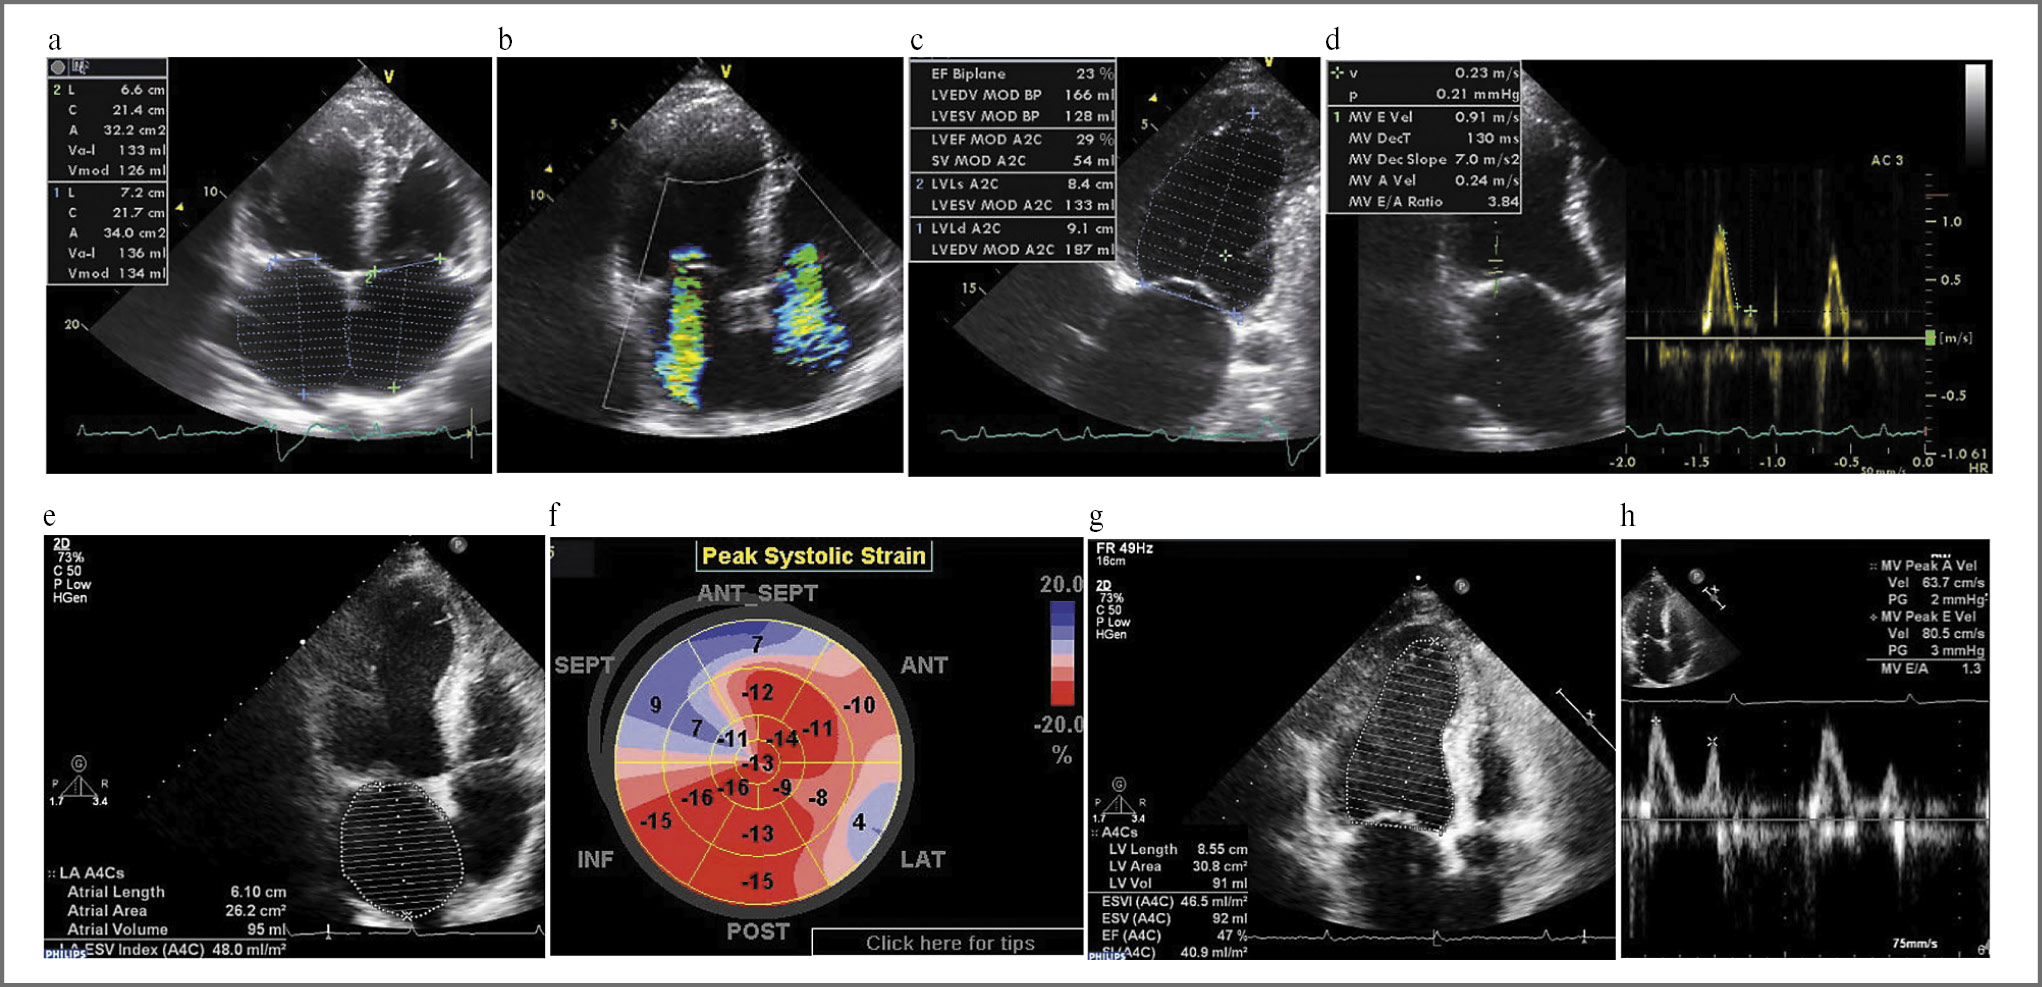

По данным ЭхоКГ (рис. 2, а–d) ЛЖ расширен: конечно-диастолический размер (КДР) 5,9 см; конечно-диастолический объем (КДО) 128 мл; конечно-систолический объем (КСО) 108 мл; толщина стенок ЛЖ не увеличена (8 мм). Систолическая функция ЛЖ значительно снижена: ФВ 23%, dp/dt 659 мм рт. ст., VTI 7,8 см, глобальная деформация –7,7%; нарушений локальной сократимости нет; левое предсердие (ЛП) 134 мл, правое 130 мл, правый желудочек (ПЖ) 4,8 см, систолическое давление в легочной артерии (СДЛА) 45 мм рт. ст., митральная и трикуспидальная регургитация II–III степени. Диастолическая функция нарушена по рестриктивному типу: Е 91 см/с, А 24 см/с, Е/А 3,8, E' 8 см/с, Е/Е' 11 S 3 см/с.

Рис. 2. Эхокардиограммы пациента К. при первой госпитализации в ФТК (октябрь 2013 г., верхние изображения) и через год после начала базисной терапии (нижние изображения).

Октябрь 2013 г.: а – выраженное увеличение объемов обоих предсердий; b – тяжелая митральная и трикуспидальная регургитация; c – резкое снижение ФВ ЛЖ (23%); d – грубое нарушение диастолической функции по рестриктивному типу (Е/А 3,6). Октябрь 2014 г.: e – уменьшение объема ЛП в 1,5 раза; f – значительное улучшение показателей глобальной деформации ЛЖ; g – возрастание ФВ ЛЖ до 47%; нормализация диастолической функции ЛЖ (У/А 1,3).

Fig. 2. Echocardiograms of patient K. at the first admission (October 2013, upper images) and a year after the start of basic therapy (lower images).

October 2013: a – marked increase in both atrial volumes; b – severe mitral and tricuspid regurgitation; c – severe decrease in left ventricle (LV) ejection fraction (23%); d – severe restrictive diastolic dysfunction (E/A 3.6). October 2014: e – 1.5-fold decrease in left atrial volume; f – significant improvement in global LV deformity; g – increase in LV ejection fraction to 47%; normalization of LV diastolic function (U/A 1.3).

Через год от начала базисной терапии (октябрь 2014 г.) ФВ ЛЖ составила 47%, объем ЛП уменьшился до 96 мл, правого предсердия – до 45 мл (см. рис. 2, e–h), ПЖ – до 3,4 см, СДЛА нормализовалось, митральная и трикуспидальная регургитация регрессировали до I степени. Сохранялся синусовый ритм. Комплексная терапия хронической сердечной недостаточности проводилась непрерывно на протяжении всего периода наблюдения, доза карведилола увеличена до 25 мг/сут, доза периндоприла – до 5 мг/сут.